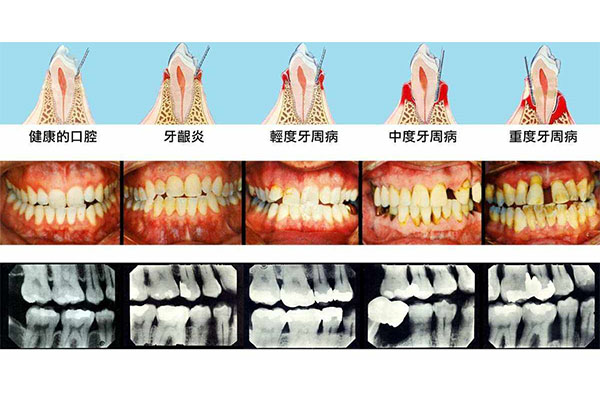

牙周炎的早期症状包括牙龈红肿、出血、口臭以及牙齿轻微松动。如果您发现这些症状,应及时采取措施,避免病情加重。中老年口腔的产品可以帮助您在早期阶段控制炎症,缓解不适。